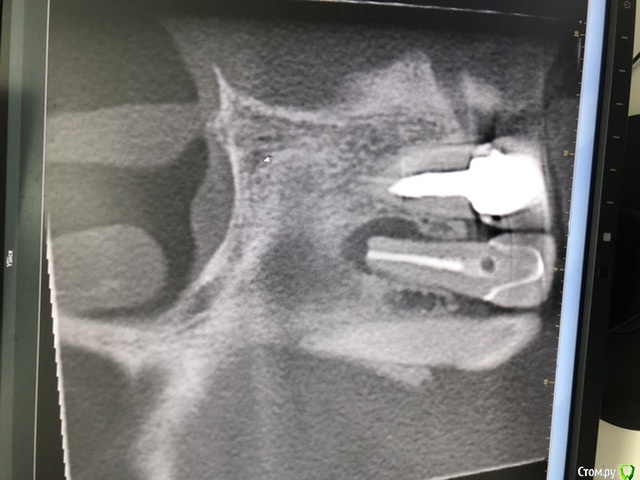

Лора777 Опубликовано 13 ноября, 2020 Автор Поделиться Опубликовано 13 ноября, 2020 Здравствуйте!Клкт посмотрите пожалуйста Ссылка на комментарий

Лора777 Опубликовано 13 ноября, 2020 Автор Поделиться Опубликовано 13 ноября, 2020 Клкт Ссылка на комментарий

Nazim_NV86 Опубликовано 13 ноября, 2020 Поделиться Опубликовано 13 ноября, 2020 До полости носа и синуса далеко. Изменения небольшие. Не вижу состояния синуса. покажите КЛКТ лору. Не можем ответить на вопрос об аллергии, т.к. нет данных про то, ложили что-то туда или нет( а если узнаем, то проверять наличие аллергии у аллерголога). Если этот зуб и виновен в рините, то только рефлекторно. Проверить это можно только его удалением (к сожалению). Ссылка на комментарий

Bier Опубликовано 16 ноября, 2020 Поделиться Опубликовано 16 ноября, 2020 там рецидив однозначно, связан с отсутствием ретроградной пломбировки канала. Ссылка на комментарий

annda Опубликовано 19 ноября, 2020 Поделиться Опубликовано 19 ноября, 2020 На джи- дефект похоже. Пусть связку по кругу прозондируют, нет ли узкого глубокого кармана, трещину исключают. Ссылка на комментарий